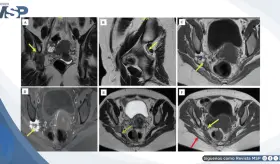

La paciente fue diagnosticada con endometriosis del nervio ciático derecho tras años de dolor incapacitante y diagnósticos erróneos.